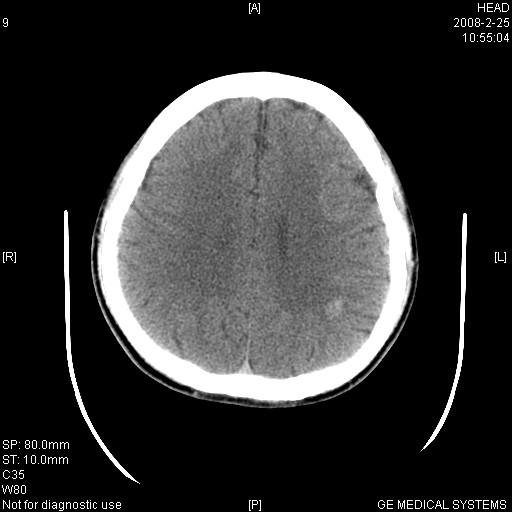

男,23岁,下颌部外伤一天,主因头痛、头晕、左面部麻木来院。两年前有外伤史,至左眼视力差。余无异常。骨窗未见异常故未上传。

左侧海绵窦区高密度肿块影,颈动脉—海绵窦瘘不排除,不过患者眼上静脉无增粗,无突眼,也不能排除血管瘤的可能,建议增强扫描。外伤病人应该有骨窗。

1、左侧海绵窦血管瘤。2、左顶后叶高密度影,建议增强扫描,血管瘤可能,脑白质异位待排。

1、左侧鞍旁海绵窦区稍高密度占位---左侧海绵窦血管瘤或脑膜瘤,以前者可能性大。2、左顶后叶高密度影,血管瘤可能,脑白质异位待排。3建议mri检查

左侧鞍旁海绵窦区稍高密度肿块,境界清楚;结合病史,不排除左侧颈内动脉海绵窦瘘可能。须与动脉瘤,海绵状血管瘤及左侧鞍旁脑膜瘤相鉴别。建议:行ct增强扫描检查,必要时行dsa检查。

1、左侧海绵窦血管瘤。2、左顶后叶高密度影,建议增强扫描,多发血管瘤可能,脑白质异位待排